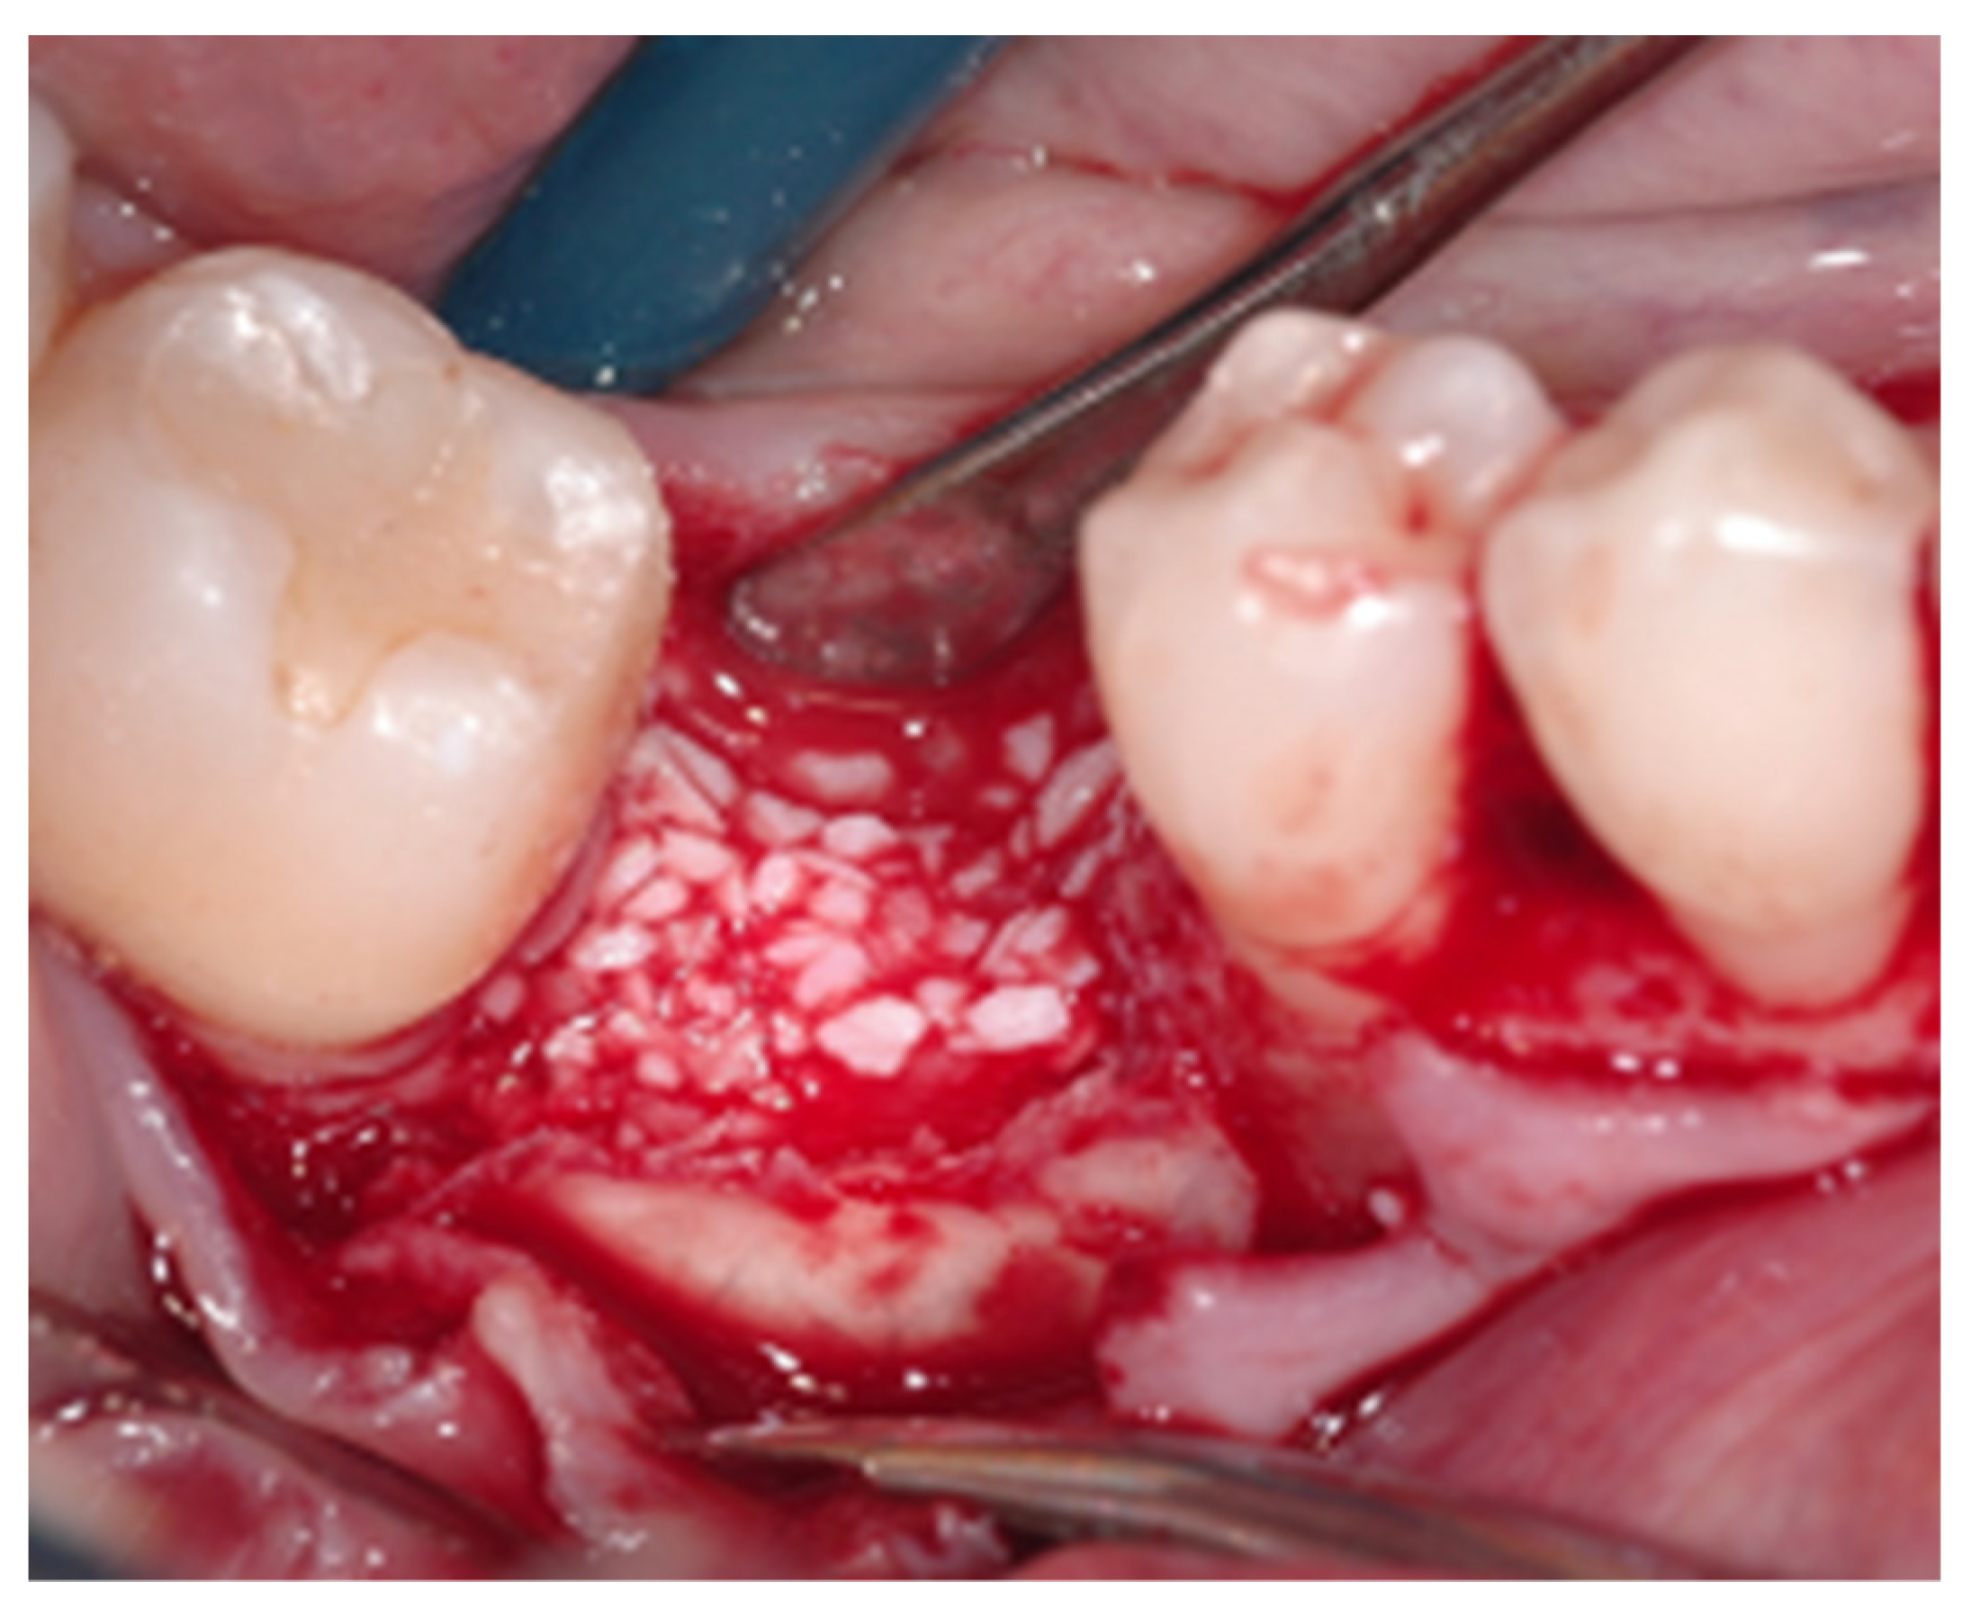

2.2. Surgical Procedure